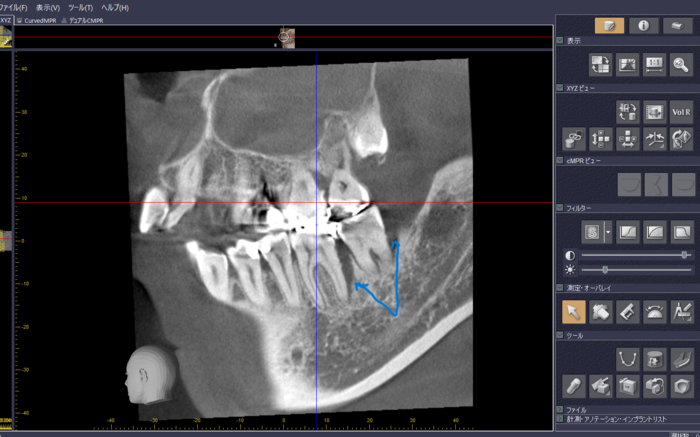

図5では、右上の奥から2番目の歯の歯茎の部分にできものが出来ている原因を見つけ出す画像です。右上の奥歯は、根が3つあるいは4つある場合が多く、通常のレントゲンではどの根が原因かを特定が難しい場合があります。CT画像で頬側の手前の根が原因だと分かりました。手前の頬側の根は、一つに見えてももう一つある場合があります。そういうことがあるので、いろいろと画面を駆使してみると、矢印で示した根の半分だけ白いものが詰まっていて半分は黒く透けてみえます。ここの部分を治療すると歯茎のできものはきれいになりました。